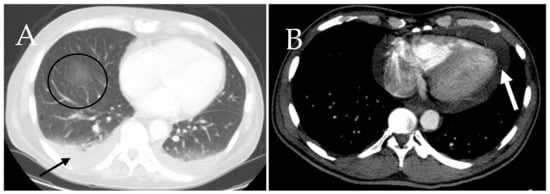

6.7. Cardiac and Respiratory